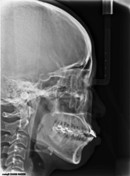

돌출입...치료는 어디에서?

어려서부터 외모 콤플렉스를 가지고 있었던 최(28 여)씨는 돌출된 입 때문에 언제나 입을 가리고 웃는다. 평소 입이 잘 다물어 지지 않아 가만히 있어도 치아가 보이고 웃을 땐 잇몸까지 많이 보여 새로운 사람을 만날 때 마다 매번…

[박은주 시민기자] 2007.09.10 09:56